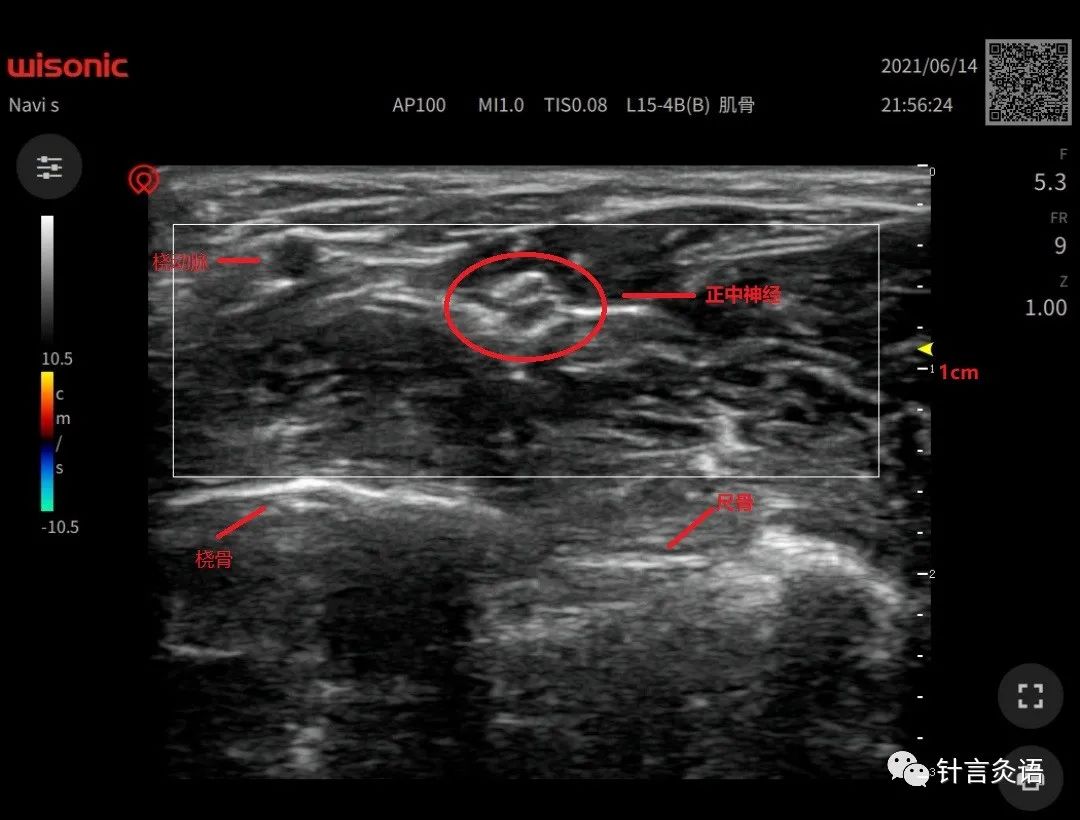

将古典的腧穴拿出来“解剖”,你会发现腧穴与解剖关系密切,神经体液内分泌反馈应激等等都是其发挥作用的途径。

把古典腧穴和现代解剖放到一起看,这就是一场巅峰聚会,必将迸发出新的思想。醍醐灌顶,也豁然开朗。